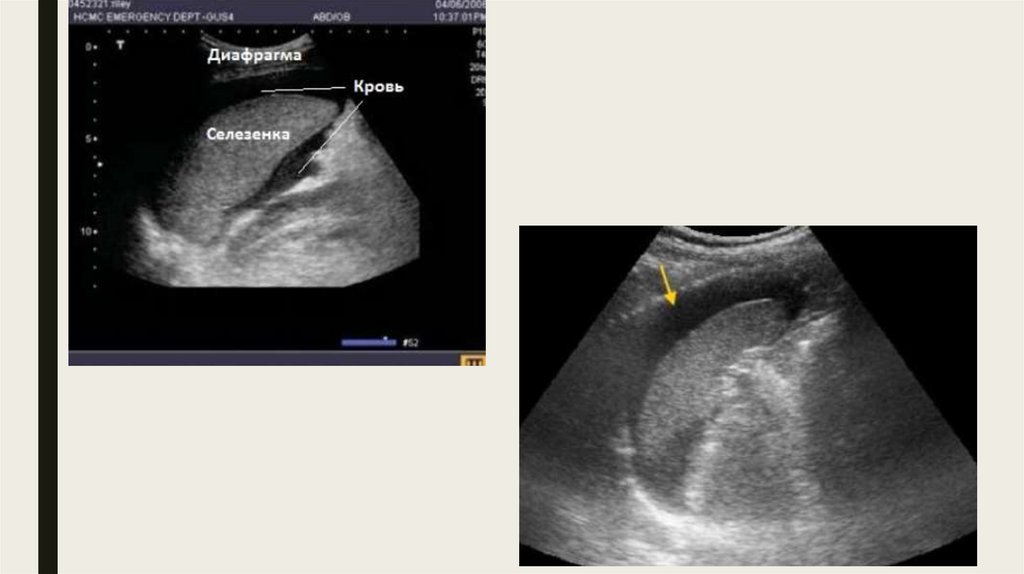

Левый верхний квадрант

Точка в малом тазу